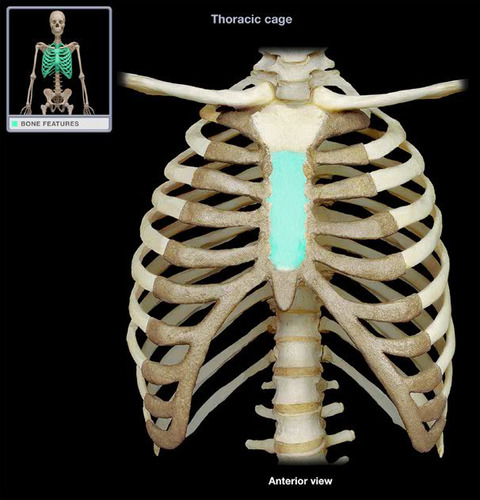

sterum

29

New cards

Sternum body

30

New cards

sternum manubrium

31

New cards

sternum xiphoid process